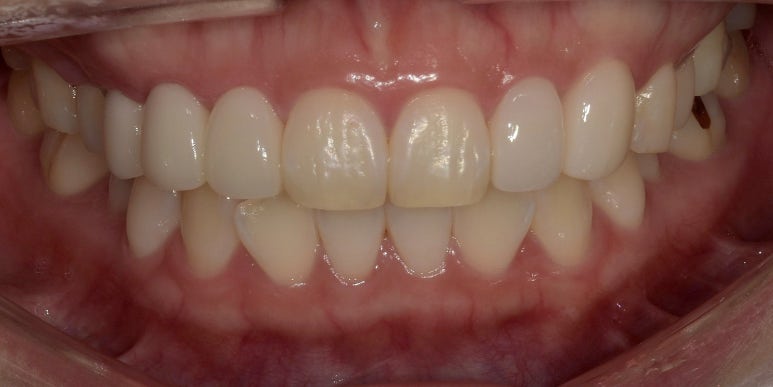

치료 후 사진

2023-04-14

치료전후사진

(전) 2023-03-02 (후) 2023-04-14

어떤가요? 결손되었던 치아는 브릿지로 완벽하게 메워졌고, 왜소치도 다른 치아와 유사하게

그리고 10번대 치아와 대칭이 잘 맞는 모습이 보이실 겁니다.

치아 색상도 전체적으로 밝아졌고, 잇몸라인도 둥글고 고르게 변한 것을 확인하실 수 있습니다.